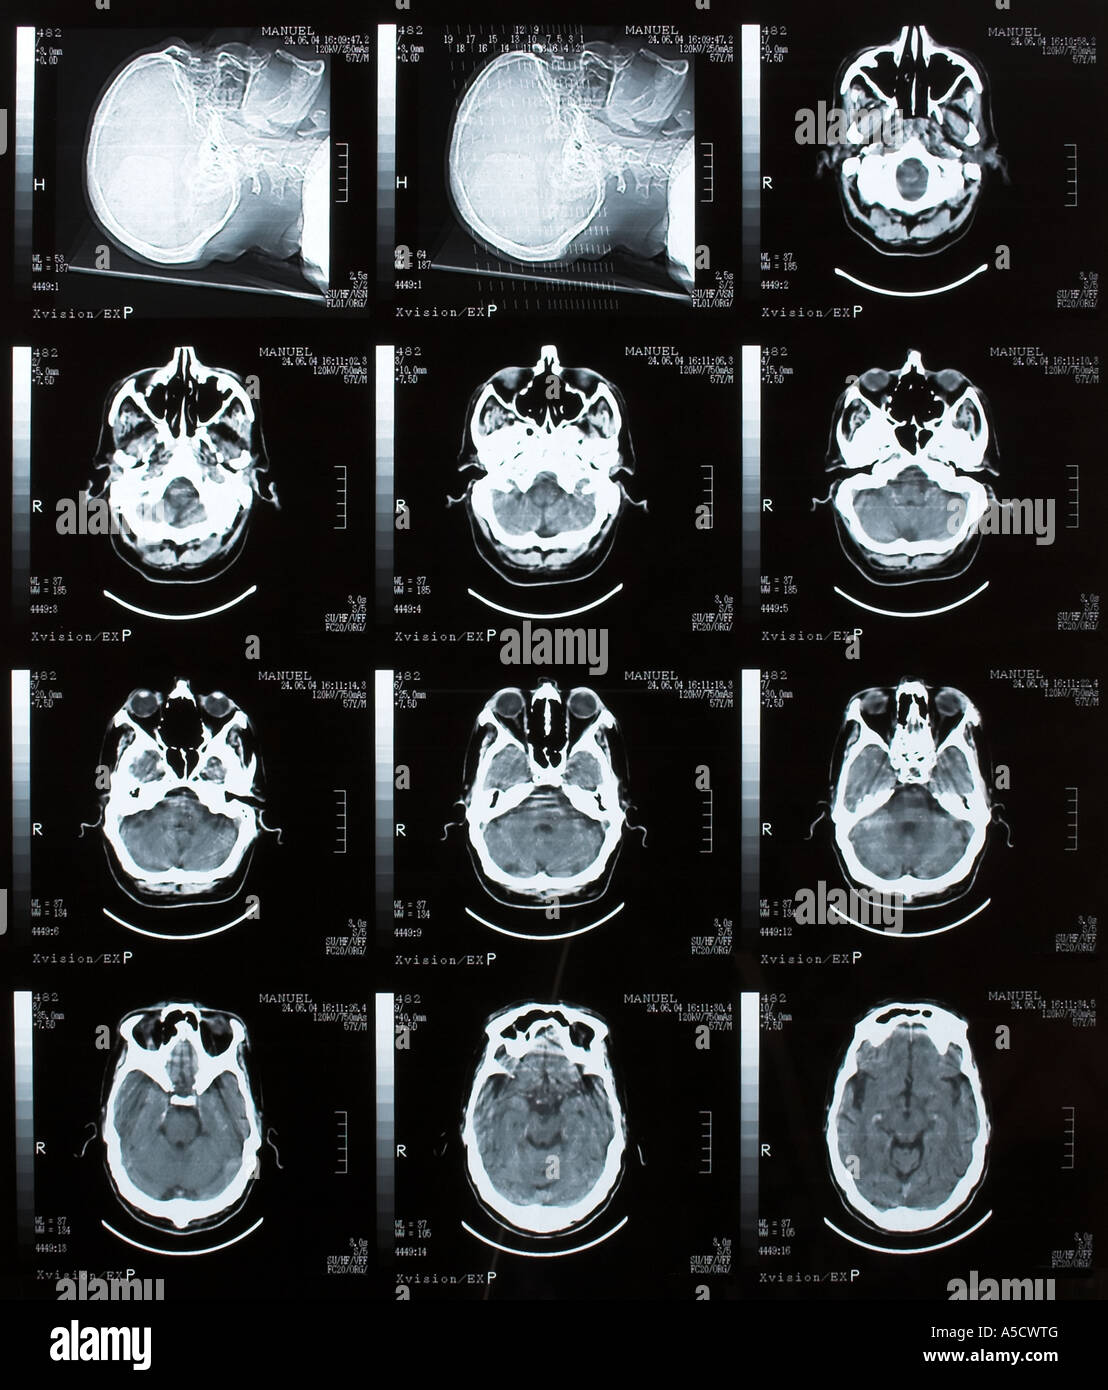

Tomodensitométrie cérébrale Banque D'Imageshttps://www.alamyimages.fr/image-license-details/?v=1https://www.alamyimages.fr/photo-image-tomodensitometrie-cerebrale-11273199.html

Tomodensitométrie cérébrale Banque D'Imageshttps://www.alamyimages.fr/image-license-details/?v=1https://www.alamyimages.fr/photo-image-tomodensitometrie-cerebrale-11273199.htmlRFA5CWTG–Tomodensitométrie cérébrale

Tomodensitométrie cérébrale Banque D'Imageshttps://www.alamyimages.fr/image-license-details/?v=1https://www.alamyimages.fr/photo-image-tomodensitometrie-cerebrale-11273202.html

Tomodensitométrie cérébrale Banque D'Imageshttps://www.alamyimages.fr/image-license-details/?v=1https://www.alamyimages.fr/photo-image-tomodensitometrie-cerebrale-11273202.htmlRFA5CWTK–Tomodensitométrie cérébrale

Tomodensitométrie cérébrale Banque D'Imageshttps://www.alamyimages.fr/image-license-details/?v=1https://www.alamyimages.fr/photo-image-tomodensitometrie-cerebrale-12412994.html

Tomodensitométrie cérébrale Banque D'Imageshttps://www.alamyimages.fr/image-license-details/?v=1https://www.alamyimages.fr/photo-image-tomodensitometrie-cerebrale-12412994.htmlRFA9P22Y–Tomodensitométrie cérébrale